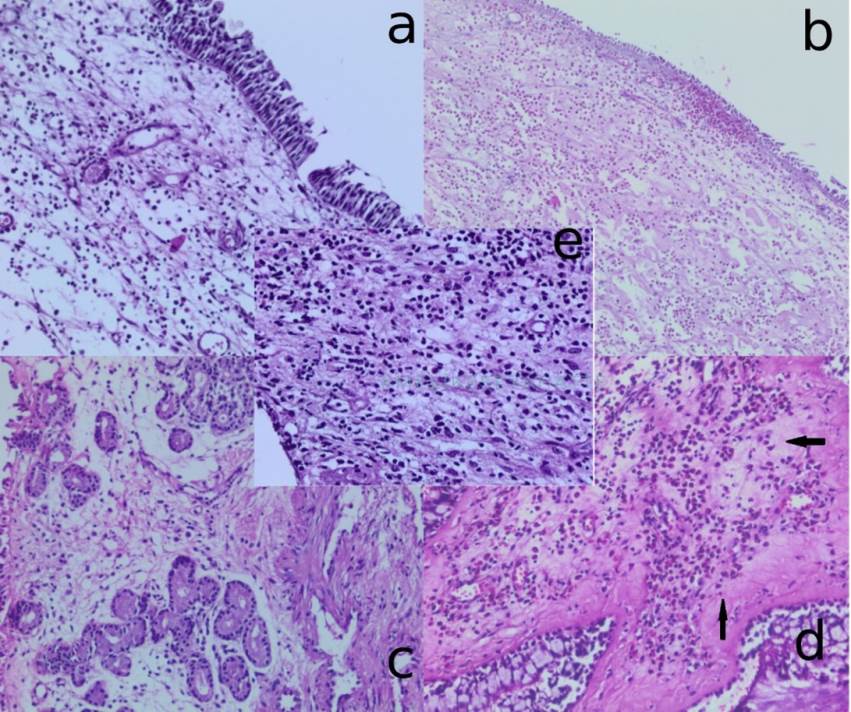

Gereçler ve Yöntem: Mart-Ağustos 2021 tarihleri arasında hastanemizde endoskopik sinüs cerrahisi yapılan 36’sı erkek, 19’u kadın toplam 55 nazal polip hastasının patolojik materyalleri incelendi. Hematoksilin ve Eozin (H&E) boyama ile histolojik alt tipler skuamöz metaplazi, epiteliyal hiperplazi gibi histolojik değişikliklerin değerlendirilmesi yapıldı. Ayrıca eozinofil, nötrofil, lenfosit oranları ve yoğunluğu gibi çeşitli inflamatuar durumları değerlendirildi. Bununla birlikte, dokularda sigara içimi ile ilgili gelişebilecek proliferatif değişiklikler immünohistokimya (İHK) yöntemi ile Ki-67 ve p53 boyama değerlendirmeleri yapılarak araştırıldı. Hastane sisteminden elde edilen klinik bilgiler, laboratuvar sonuçları ve Lund-Mackay sınıflaması verileri dahil edildi. Çalışmada R 4.2.2 programı kullanılarak Ki-Kare ve Fisher testleri ile T-testi analizleri gerçekleştirildi.

Bulgular: Hastaların yaş ortalaması 37,22±16.96’dir. Bunlardan 34’ü (61,82%) sigara içmezken, 21’i (38,18%) sigara içmekteydi. Sonuçlarımızda sigara içenlerde ve Lund-Mackay sınıflaması puanı yüksek olanlarda eozinofilik infiltrasyon ile anlamlı bir ilişki gösterdi (p<0.05). Ayrıca, Lund-Mackay puanı yüksek olanlarda eozinofilik ve lenfoplazmositik inflamasyon türleri ile de anlamlı korelasyon saptandı (p<0.05). Nazal poliplerde skuamöz metaplazinin bulunması ile Ki-67 ve p53 immünhistokimyasal boyanma skorları arasında anlamlı ilişki bulunurken, epiteliyal hiperplazi ile bu değerler arasında ilişki bulunmadı.